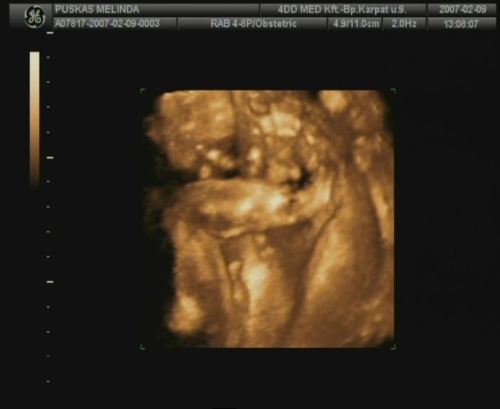

Sziasztok, megjöttem a 4D-ről. Sajnos most nincs időm a dvd-ről kimentegetni a képeket, de a telcsivel azt a hármat lefotoztam, amit kaptunk, remélem, hogy kivehető lesz azért számotokra a lényeg!

A szülésem dátuma is 2007.05.25.-re módosult, illetve a tickeremet is átjavítottam esszerint! :)

Ja lányok, csak, hogy untassalak titeket, tegnap az egyik barátom megmutatta, hogy kell dvd felvételről kimenteni képeket, így Domcsiról lementettem pár tuti képet! Mellékelem, remélem nem baj:

Untatni? édes képekkel lehet szerinted minket untatni? Ezek nagyon cukik! Édes nagyon a babád!

Az ásítós, meg az első, a szemvakargatós, az igen :)

olyan mintha azt akarná mondani, hogy minek keltettetek fel, hát hagyjatok már békén, itt már aludni se lehet?

Hát nagyon cuki, az ilyen képekkel nem lehet betelni :)